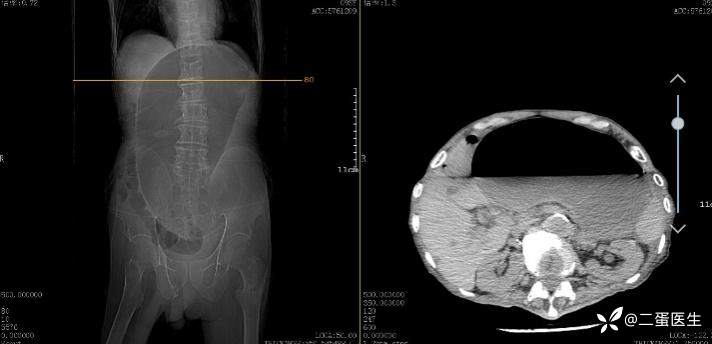

辅助检查: 影像学检查见巨大胃泡影,提示胃扭转伴胃扩张。

胃扭转也可以根据其异常旋转的轴的不同而分为器官轴(长轴)型(organoaxial volvulus)和系膜轴(短轴)型(mesenteroaxial volvulus)。器官轴型胃扭转是指胃以贲门与幽门部连线为轴发生的旋转,胃窦向前上方,胃底向后下方旋转,其结果是胃大弯以倒置位而位于胃小弯的上方,如上文中图1所示。器官轴型胃扭转是临床中最常见的胃异常旋转类型,约占胃扭转病例的60%,胃绞窄性坏死更常见于这种类型的胃扭转,发生率超过30%。系膜轴型胃扭转是指胃以连接胃大弯和胃小弯的垂直线为轴发生的旋转,胃窦移位到贲门部上方。系膜轴型胃扭转程度上通常<180°,且旋转通常与继发性解剖缺陷无关。